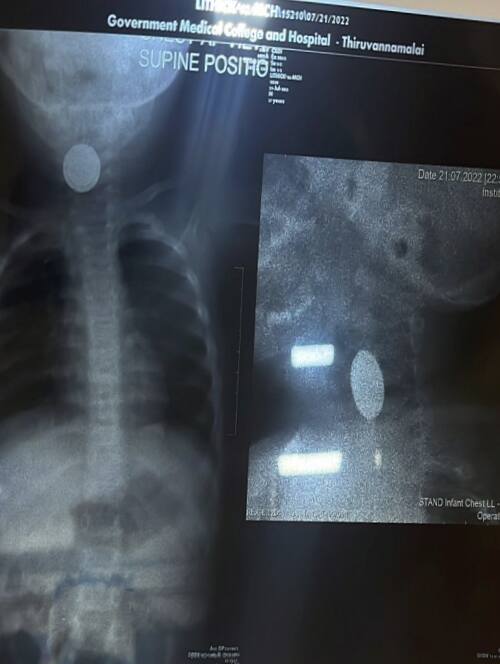

அதன் பிறகு குழந்தை பேட்டரியை விழங்கியது தெரியவந்துள்ளது. அதனைத்தொடர்ந்து அவர்கள் உடனடியாக சிறுவனை திருவண்ணாமலை அரசு மருத்துவக்கல்லூரி மருத்துவமனைக்கு சிகிச்சைக்காக அழைத்து வந்தனர். பின்னர் உடனடியாக மருத்துவர்கள் குழந்தையை எக்ஸ்ரே செய்து பார்த்தபோது தொண்டையில் உணவுக்குழாய்க்கும், மூச்சுக்குழாய்க்கும் இடைப்பட்ட பகுதியில் பேட்டரி சிக்கியது தெரியவந்தது. அதன் பிறகு அறுவை சிகிச்சை பிரிவிக்கு குழந்தையை அழைத்து செல்லப்பட்டார். இதையடுத்து காது, மூக்கு, தொண்டை துறைத் தலைவர் இழஞ்செழியன் தலைமையில் மருத்துவர் கமலக்கண்ணன், மயக்கவியல் துறைத்தலைவர் பாலமுருகன், மயக்கவியல் நிபுணர் பாலகிருஷ்ணன் மற்றும் மருத்துவக்குழுவினர் குழந்தையின் தொண்டையில் சிக்கிய வட்டவடிவ பேட்டரியை அகற்றும் நடவடிக்கையில் ஈடுபட்டனர். சிறுவனுக்கு மயக்க மருந்து அளித்து அறுவை சிகிச்சையின்றி லாரிங்கோஸ்கோபி என்ற முறையில் வட்டவடிவலான பேட்டரியை அகற்றினர்.